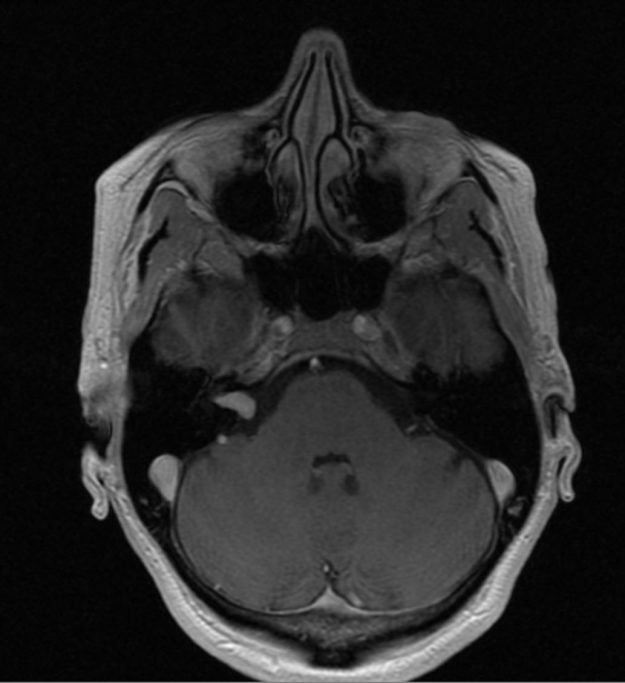

Μηνιγγίωμα περιοχής Επίφυσης

Ασθενής γυναίκα, 52 ετών η οποία παρουσίασε υπακουσία και επεισόδια πάρεσης του προσώπου. Ο απεικονιστικός έλεγχος με μαγνητική τομογραφία ανέδειξε ευμεγέθη όγκο στην περιοχή της επίφυσης (κωνάριο) με πίεση επί του μεσολοβίου, του τετραδύμου πετάλου και λοιπών εν’ τω βάθει δομών. Διενεργήθη δεξιά ινιακή, διασκηνιδιακή, διαδρεπανική προσπέλαση και ολική αφαίρεση της βλάβης. Η μετεγχειρητική αξονική…